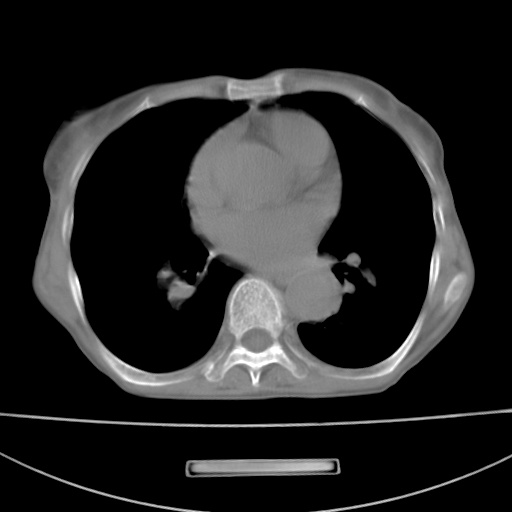

患者 女 67岁,反复咳嗽咳痰2年,加重伴喘及双下肢浮肿1月

诸大血管及f肺门血管增粗迂曲.左下肺多发薄壁空腔影.部分非也透亮度增高.薄曾扫描可区分肺气肿类型.考虑1.慢性支气管炎 2.左下肺支气管扩张 3.肺气肿 4 肺动脉高压5.是否有先心病病史